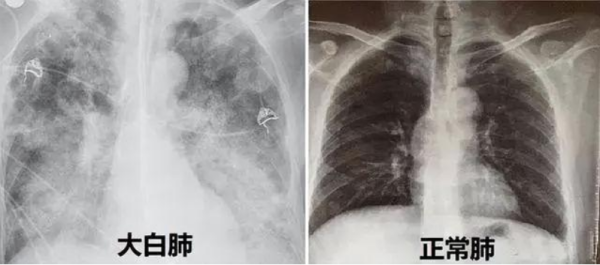

就诊,经检查,胸片呈现“白肺”状态,如果治疗抢救不及时,很容易造成不可挽回的后果。

“患者入院时,我们给他做了详细的检查,发现老人的血氧饱和度只有70%,呼吸频率增快约30次/分,CT检查双肺呈现毛玻璃样影,病灶边缘模糊不清,双肺呈现‘白肺’状态,血气分析提示呼吸衰竭,病情十分危重。”立博体育|实时赛事直播与比分|权威专家分析与体育竞猜平台

全科医学科主任、主任医师张辉容介绍,正常人的血氧饱和度通常在95%到100%之间,当下降到90%以下,人体可能因大脑氧气不足而出现昏睡,低于80%则可能对重要器官造成损害,甚至会直接导致窒息、休克、死亡等悲剧的发生。像张爷爷这种情况已经非常危急,幸好护士的电话随访给他争取了抢救治疗的时间,后续医护人员对老人进行了呼吸机辅助呼吸、俯卧位通气、抗感染、营养治疗、肺康复等综合救治,老人的病情开始好转,成功撤掉呼吸机,“白肺”开始吸收,血氧饱和度逐渐恢复到95%以上。

(图片来源网络)

“CT影像检查显示白肺,说明肺炎病变范围较广,甚至几乎累及整个肺部,老人已经发生呼吸衰竭,严重时甚至会出现急性呼吸窘迫综合征。”张辉容主任介绍,肺部是由肺泡组成的,肺泡里边充满了空气,在CT检查时,它通常显示为灰黑色。由于感染、创伤各种原因导致的肺泡里出现炎症,或者感染有渗出液时,肺泡就被这些渗出液或者炎性细胞所填充,有很多沉积物、甚至实变,肺部透过X线的能力大幅减弱,在胸片或者CT上,会看到肺的整个组织不是灰黑色,而是白色,就是大家通常说的“白肺”,这类情况死亡率较高。但白肺是可以预警的,及时发现缺氧状况,及时救治是关键。